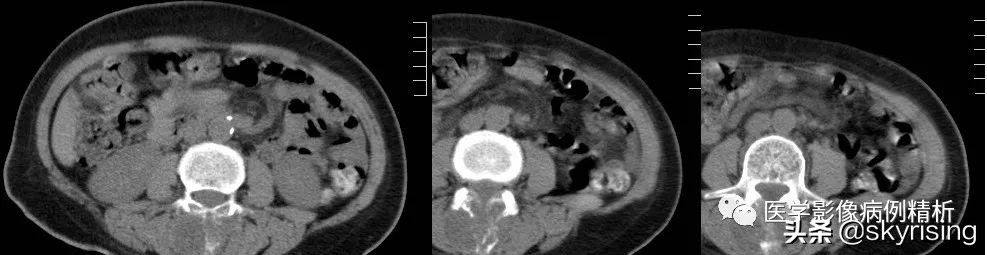

CT

CT:红色箭头所示为腰3椎体附件包括棘突、双侧椎弓根骨质呈溶骨性破坏, 其内见多发点状、条形骨瘠残留,相应部位见团块状稍低密度影,大小约3.5cmx2cm,边界欠清,密度欠均匀。